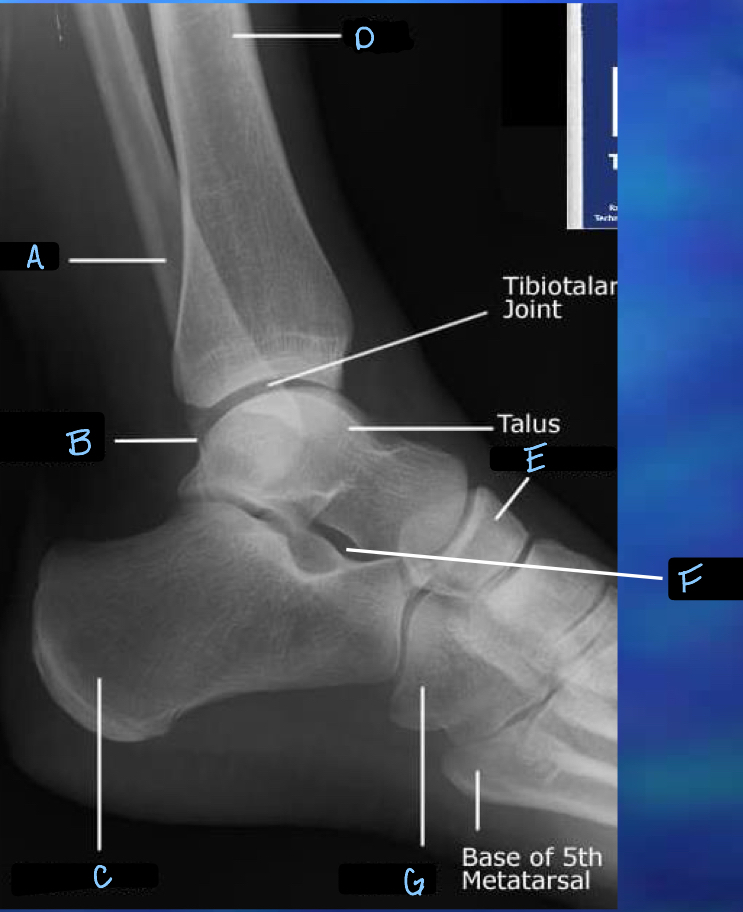

8

Q

What is A?

A

fibula

9

What is B?

lateral malleolus

10

What is C?

calcaneum

11

What is D?

tibia

12

What is E?

navicular

13

What is F?

sinus tarsi

14

What is G?

cuboid